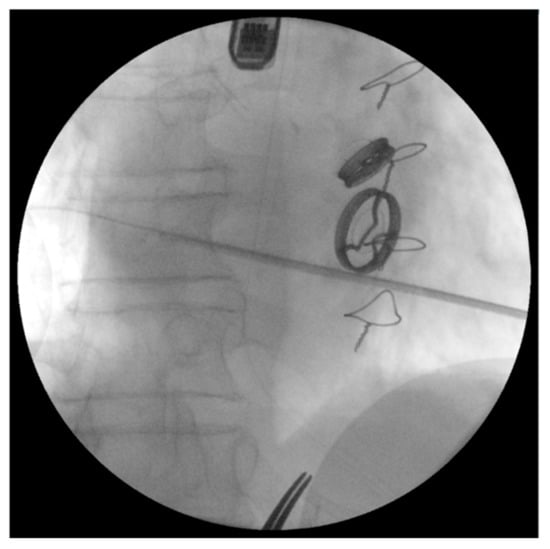

- Zorinas, A.; Janušauskas, V.; Davidavičius, G.; Šimakauskas, R.; Puodžiukaitė, L.; Zakarkaitė, D.; Bilkis, V.; Čypienė, R.J.; Samalavičius, R.S.; Onorato, E.M.; et al. Retrospective analysis of single-centre early and midterm results of transapical catheter based mitral paravalvular leak closure with a purpose specific device. Postpy Kardiol. Interwncyjnej 2018, 14, 167–175. [Google Scholar]

- Onorato, E.M.; Muratori, M.; Smolka, G.; Zakarkaite, D.; Mussayev, A.; Christos, C.P.; Bauer, F.; Gandet, T.; Luca, G.; Martinelli, M.D.; et al. Midterm procedural and clinical outcomes of percutaneous paravalvular leak closure with the Occlutech Paravalvular Leak Device. Eurointervention 2020, 15, 1251–1259. [Google Scholar] [CrossRef] [PubMed]